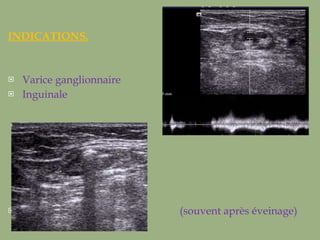

INDICATIONS. Varice ganglionnaire Inguinale  (souvent après éveinage)

INDICATIONS. Varice ganglionnaireInguinale (souvent après éveinage)